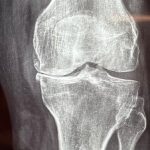

Η οστεοαρθρίτιδα είναι η συχνότερη αιτία για την οποία γίνονται οι αρθροπλαστικές στο γόνατο.

Η άρθρωση αποδιοργανώνεται, ο χόνδρος που καλύπτει τις αρθρικές επιφάνειες καταστρέφεται και εγκαθίσταται προοδευτικά επιδεινούμενος πόνος και δυσκαμψία της άρθρωσης.

Μία απλή ακτινογραφία επιβεβαιώνει την διάγνωση και την έκταση της βλάβης.